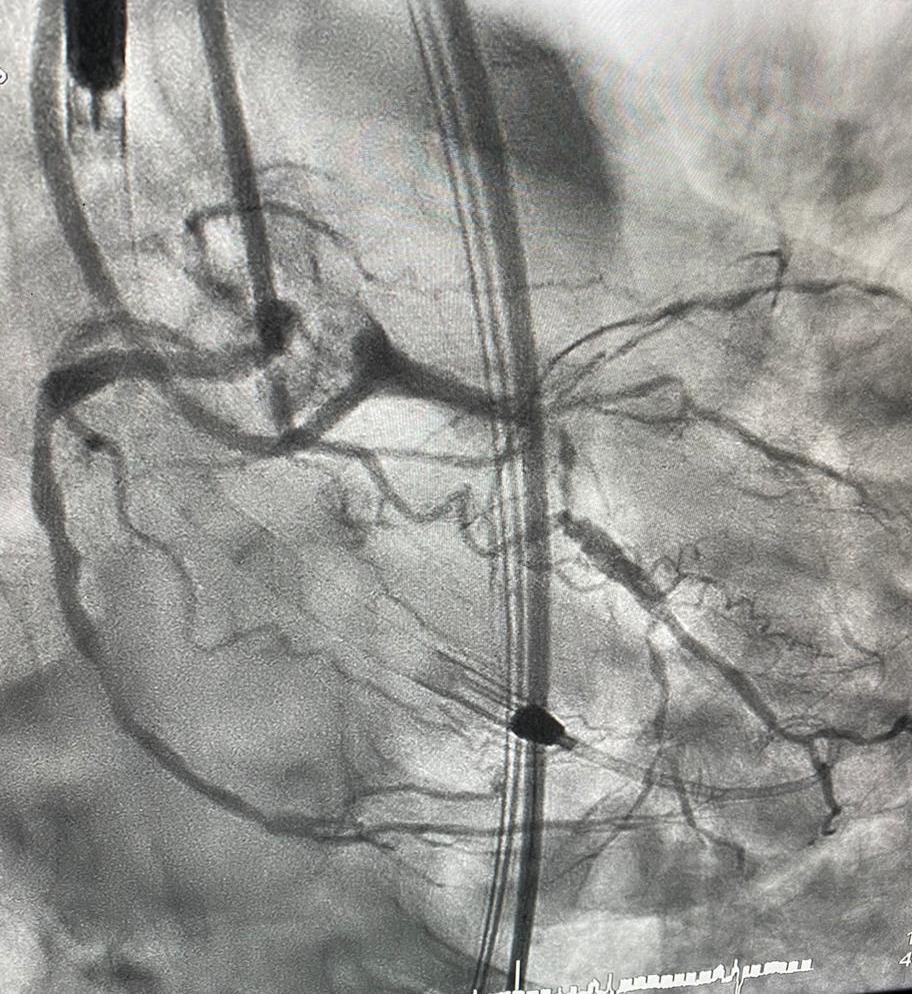

تقنية إمبيلا تنقذ ستينيًا من ضيق الشرايين بسعود الطبية

سجلت مدينة الملك سعود الطبية ممثلة بمركز صحة القلب نجاح أول عملية قسطرة قلبية لعلاج ضيق الشرايين باستخدام أحدث الأجهزة القلبي إمبيلا لمريض ستيني يعاني من تضيقات في عدة شرايين، وتمت إزالة الجهاز بنجاح بعد عملية القسطرة القلبية، الذي يسهم في تقليل مخاطر عمليات القسطرة القلبية المعقدة.

وأوضح مدير المركز د. مبارك الدوسري بأن أهمية استخدام الجهاز تكمن في توفير الدعم اللازم وتسهيل مهمة عمل الفريق الطبي أثناء عمليات القسطرة القلبية عالية الخطورة، وذلك بضخ الدم البطيني مباشرة للأورطى والشرايين القلبية، بحيث يتم تمرير هذا الجهاز عن طريق الفخذ وتثبيته في الجهة اليسرى من القلب بواسطة القسطرة القلبية.

إزالة الجهاز بنجاح بعد القسطرة

ونوه د. الدوسري بأنه تمت إزالة الجهاز بنجاح بعد عملية القسطرة القلبية، وأن المريض حاليًا بحالة صحية مستقرة وجيدة، ويستعد للخروج من المدينة خلال الأيام القليلة المقبلة.